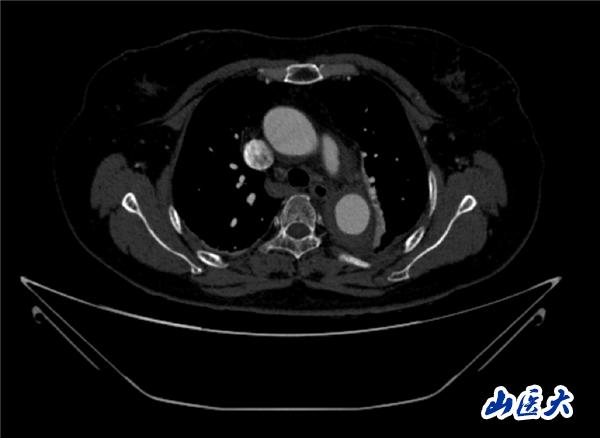

首例患者是一位55歲的女性,她患有高血壓約2年時間,平時也會規律服用多種降壓藥,但血壓控制始終不盡人意。2023年4月下午,她出現不明原因的頭痛,在家拔罐緩解少許便未到醫院就醫,次日凌晨突感胸悶、胸背疼痛伴有呼吸困難等癥狀、家人急忙撥打了120,把患者送入醫院急診科進行救治,醫生在急診科行胸腹主動脈CTA時,顯示主動脈弓部-降主動脈及腹主動脈壁間血腫,遂收治入醫院血管外科,患者入院10天后復查血腫仍未有改善,依然伴有胸背部疼痛等不適,如不進一步處理,可能發展為夾層危及生命,患者及家屬經過與醫生團隊了解溝通,決定進行創傷小、恢復快的介入手術治療。張瑋教授、符偉國教授、董紅霖教授及其血管外科團隊(閆盛、常文凱、田琴琴)共同商討手術方案,最終確定使用Zipper?一體式主動脈弓覆膜支架系統,行胸主動脈覆膜支架腔內隔絕術+無名動脈、左頸總動脈、左鎖骨下動脈分支重建術為患者進行治療。董紅霖教授及其血管外科團隊根據患者術前頭顱CT平掃提示雙側側腦室旁缺血灶,血壓控制不穩定,屬夾層壁間血腫非典型夾層等風險點,制定了完整的手術方案,術中經股動脈置入Zipper支架主體,經預留導絲超選無名動脈,并確保主體支架對位準確,順利置入左頸總動脈、左鎖骨下動脈支架,重建弓上三分支。手術過程非常順利。術后觀察主動脈及分支覆膜支架定位準確;無內漏;分支支架通暢,動脈供血正常。

術前CTA